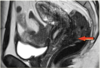

Q. Las siguientes imágenes muestran una patología Epifisiolisis o Epifisiolistesis, ¿Cuál es, por qué y que datos son los que señalan las fechas?

R: Epifisiolisis ya que no está desplazada, la flecha blanca señala la placa de crecimiento ensanchada e irregular, la punta de flecha derrame sinovial.